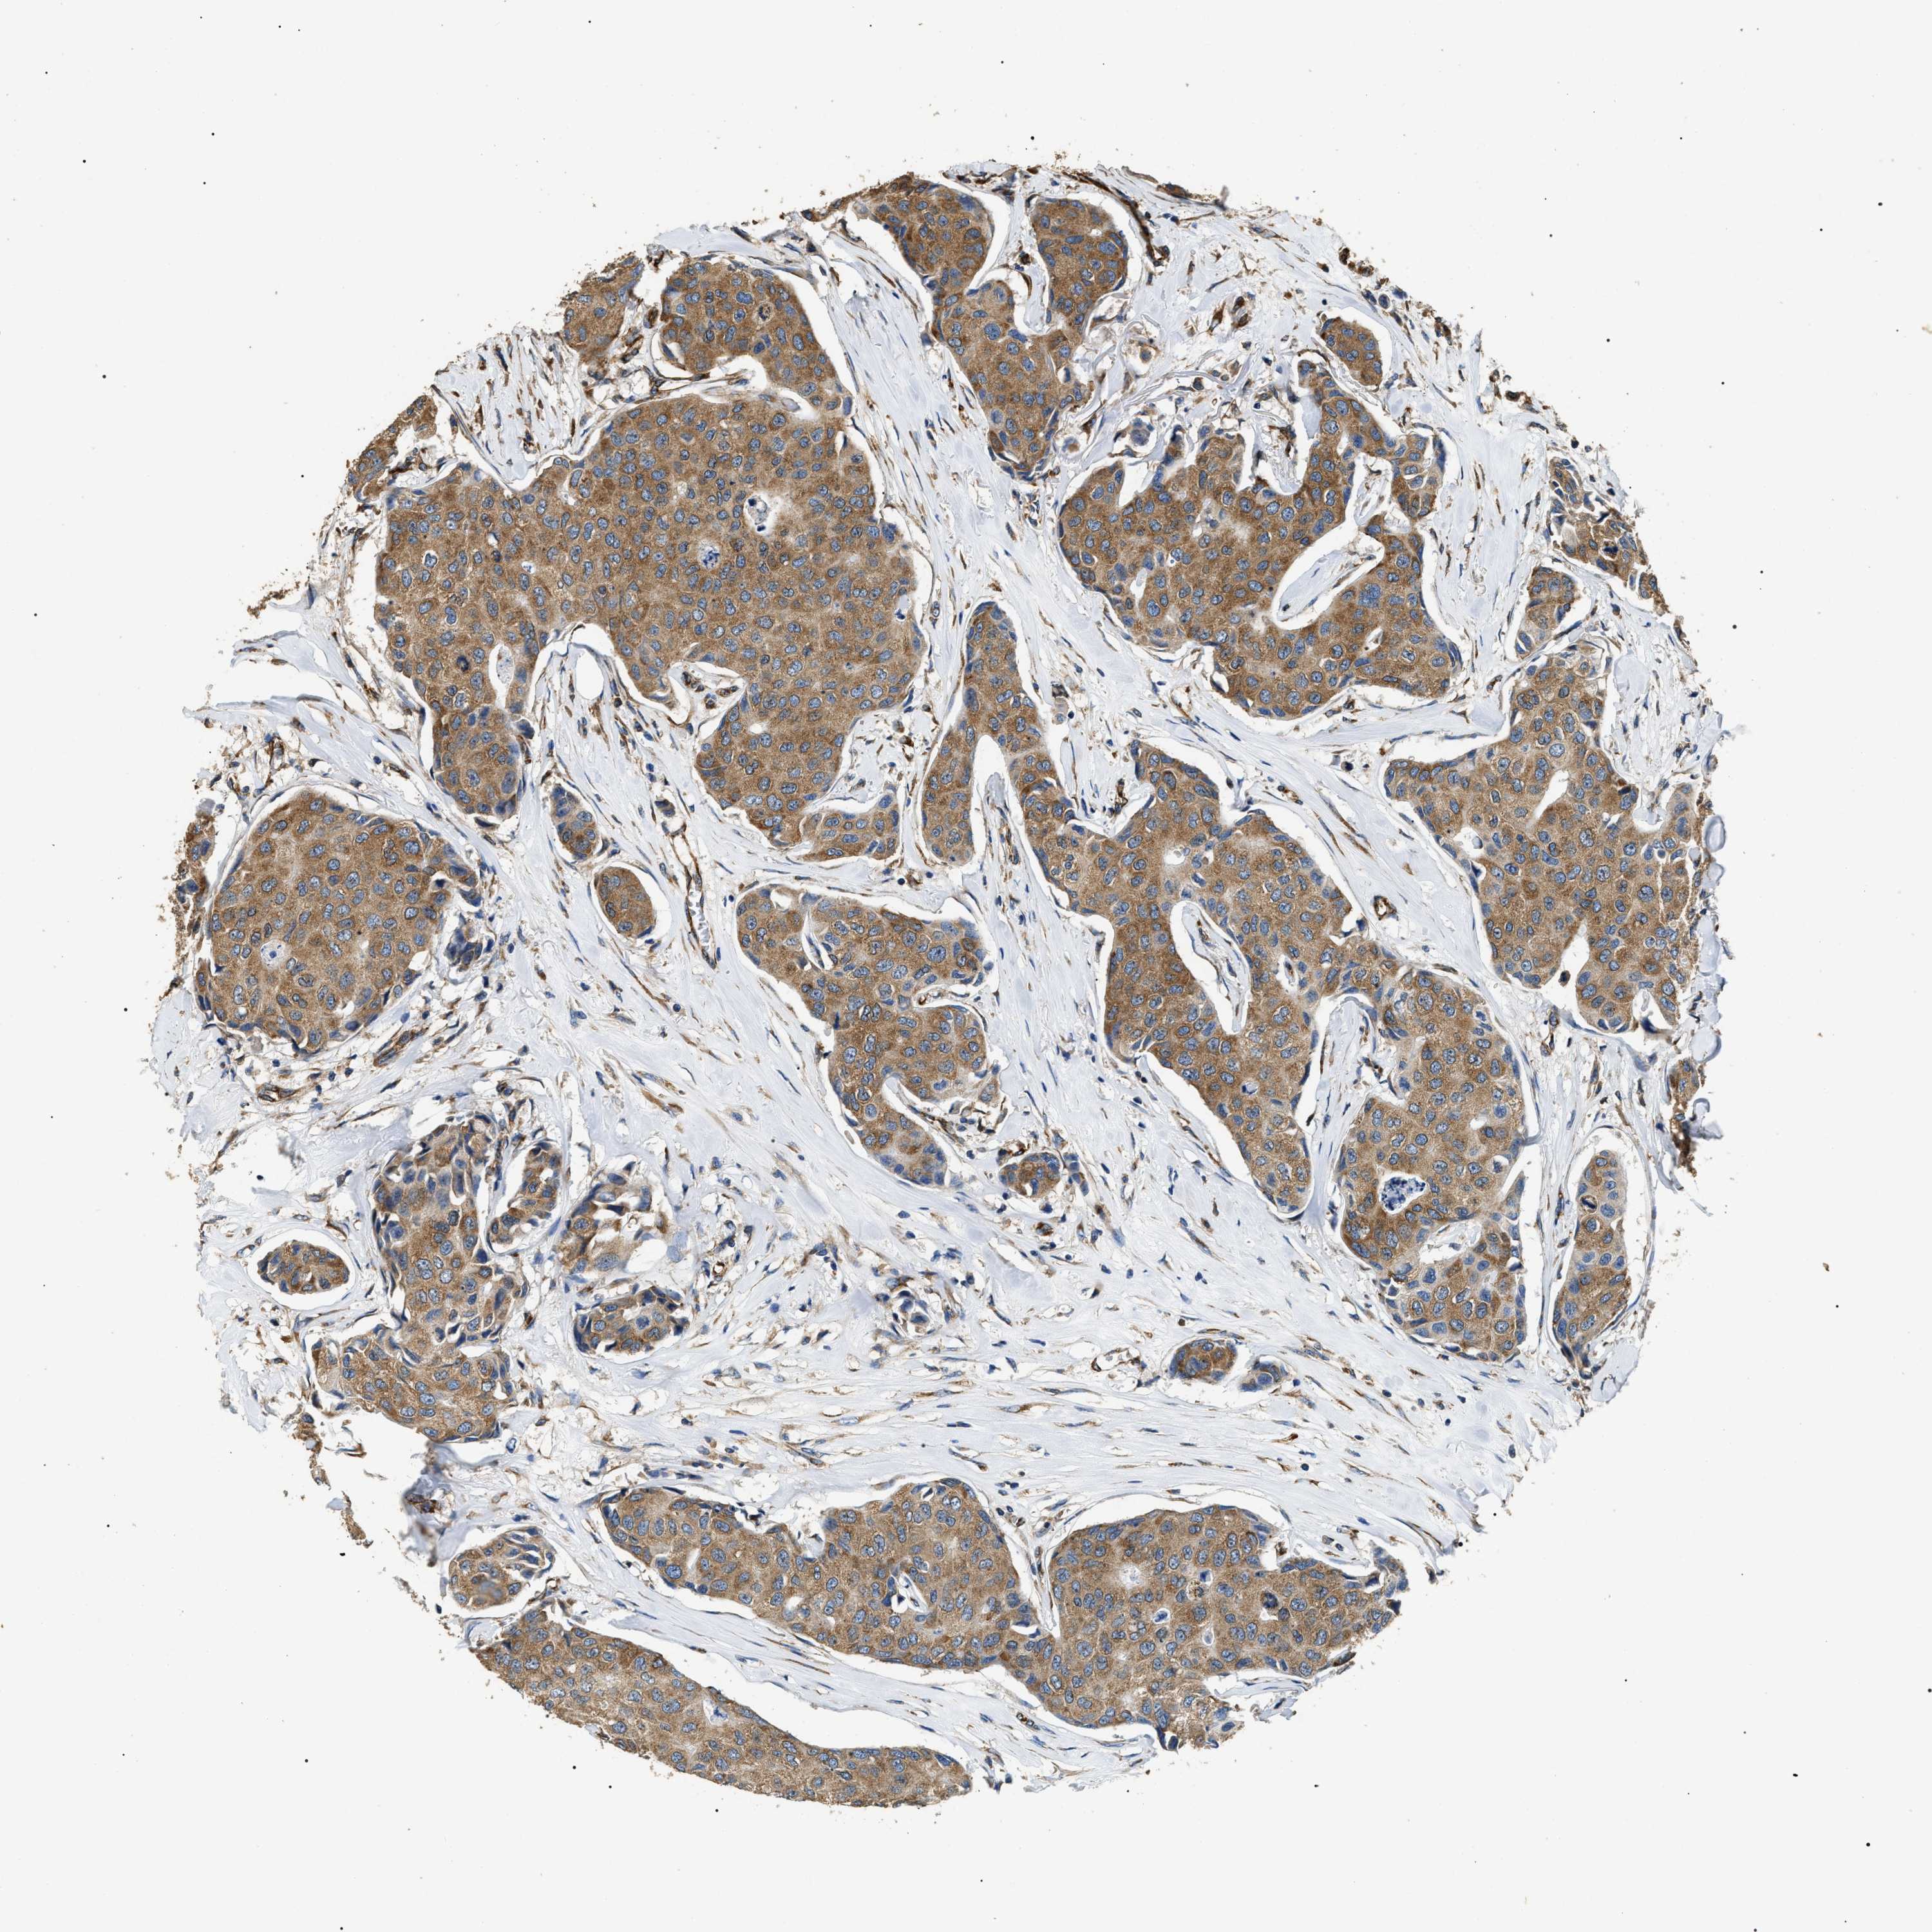

CANCER BREAST CANCER Show tissue menu

BRCA TCGA BRCA VALIDATION PROTEIN EXPRESSION